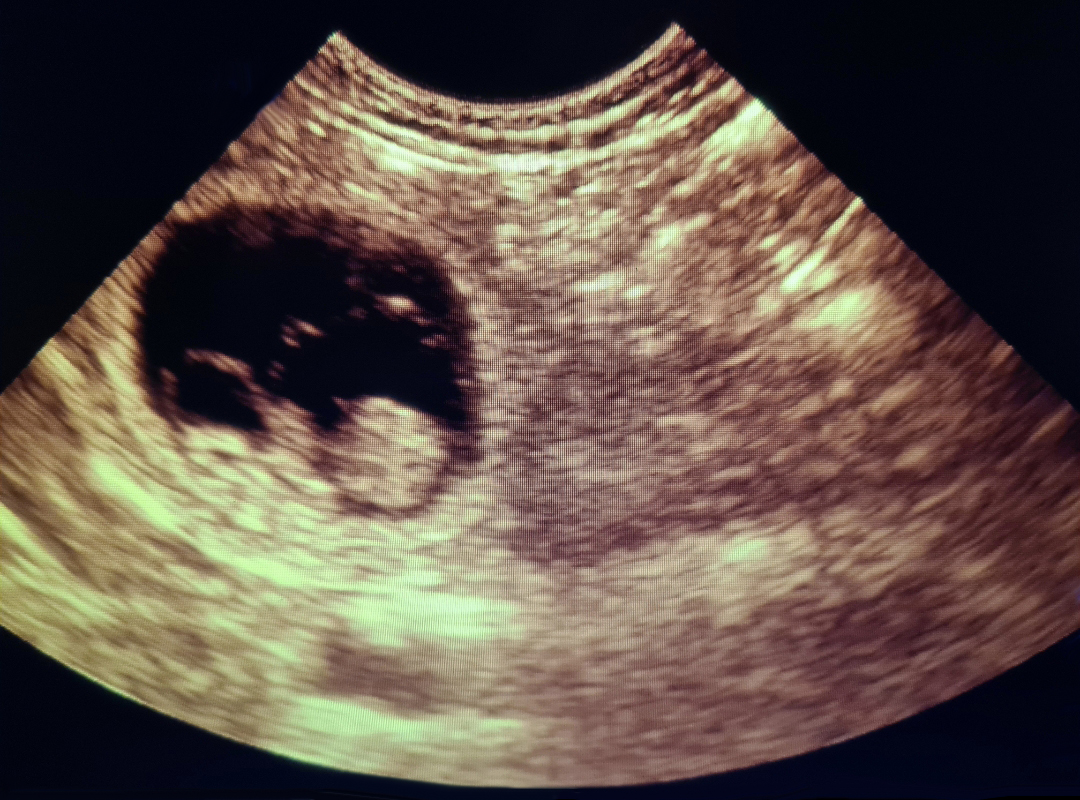

If you believe your pet may be pregnant, we offer gentle and completely painless ultrasound scans to help confirm pregnancy in dogs and cats. These scans can typically be performed from around 28 days after mating.

During the scan, your pet remains calm and comfortable with you gently holding them. A small amount of gel is applied to their abdomen, and a handheld probe is moved carefully over the area to view any developing puppies or kittens.

Using a reliable Scan Pad Ultrasound scanner, Julie can confirm pregnancies and provide you with email copies of any images showing puppies.